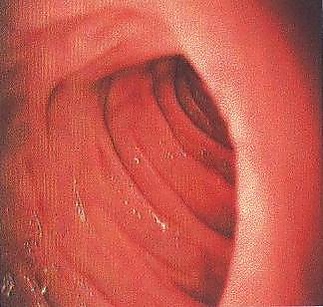

- Начальная часть двенадцатиперстной кишки расширена — это ампула, или луковица (лат. ampulla). Слизистая ампулы, как и в привратнике желудка, имеет продольную складчатость, тогда как в остальных отделах двенадцатиперстной кишки складчатость циркулярная. Это связано с тем, что ампула развивается из передней первичной кишки, а остальная двенадцатиперстная кишка — из средней.